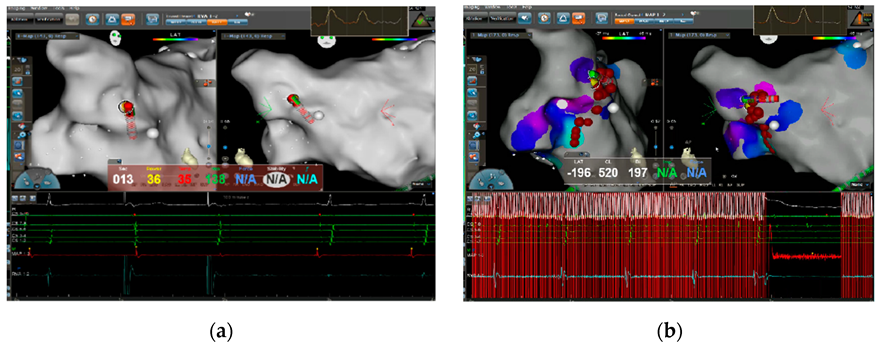

2.4. High-Frequency Stimulation-Guided Endocardial Catheter Ablation of GPs in the LA

2.5. Anatomically Guided Endocardial Catheter Ablation of GP in LA